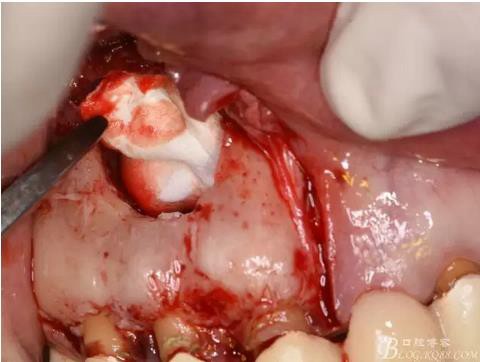

圖11.摘除囊壁后形成的骨腔

圖12.超生骨刀切除12根尖

圖13.根尖倒預備